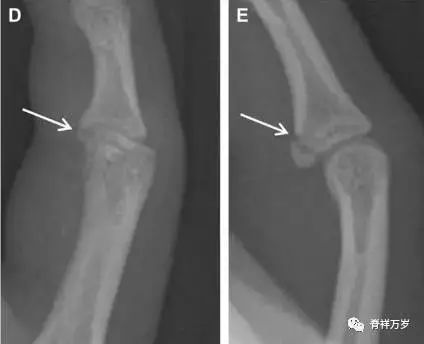

无移位的桡骨头/颈骨折

多发生于摔倒时,手掌撑地,受到轴向、外翻应力所致。常规的前后位片容易漏诊,常需加拍内斜位、外斜位、桡骨头-肱骨小头位片。后脂肪垫可见(位于鹰嘴窝内,一般不可见)和/或前脂肪垫抬高常提示骨性损伤。

图 2 桡骨头骨折。前后位(A)和侧位(B)片示后脂肪垫抬高(黑色箭头),前脂肪垫抬高(白色箭头),呈「帆船征」,其它表现正常;外斜位(C)和桡骨头–肱骨小头位(D)示桡骨头关节内骨折线(虚线黑箭头)累及桡骨颈(虚线白箭头)。